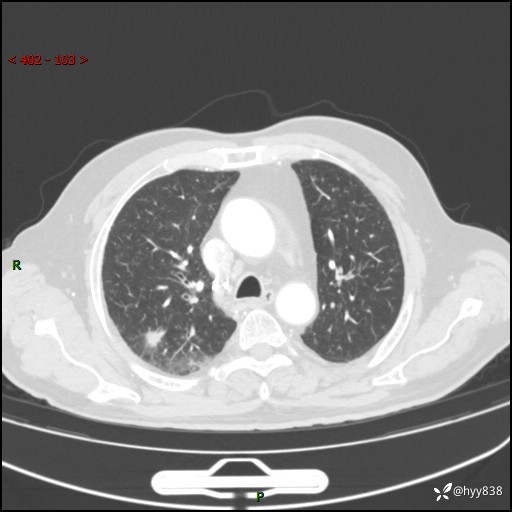

现病史:患者4月前无明显诱因后背正中间疼痛,间断阵痛,无低热、咳嗽,盗汗、咯血、胸痛、喘气等不适,2024-2-25当地市第二人民医院胸部CT提示“1.双肺感染病变;2.右肺中叶结节灶;3.双肺肺气肿并肺大泡4.主动脉及冠脉硬化,今为求明显结节性质遂来我院门诊就诊,门诊以“肺占位”收治入院。 起病以来,患者精神饮食睡眠一般,大小便正常,体力体重无明细变化。

胸部CT复查(2024.7)